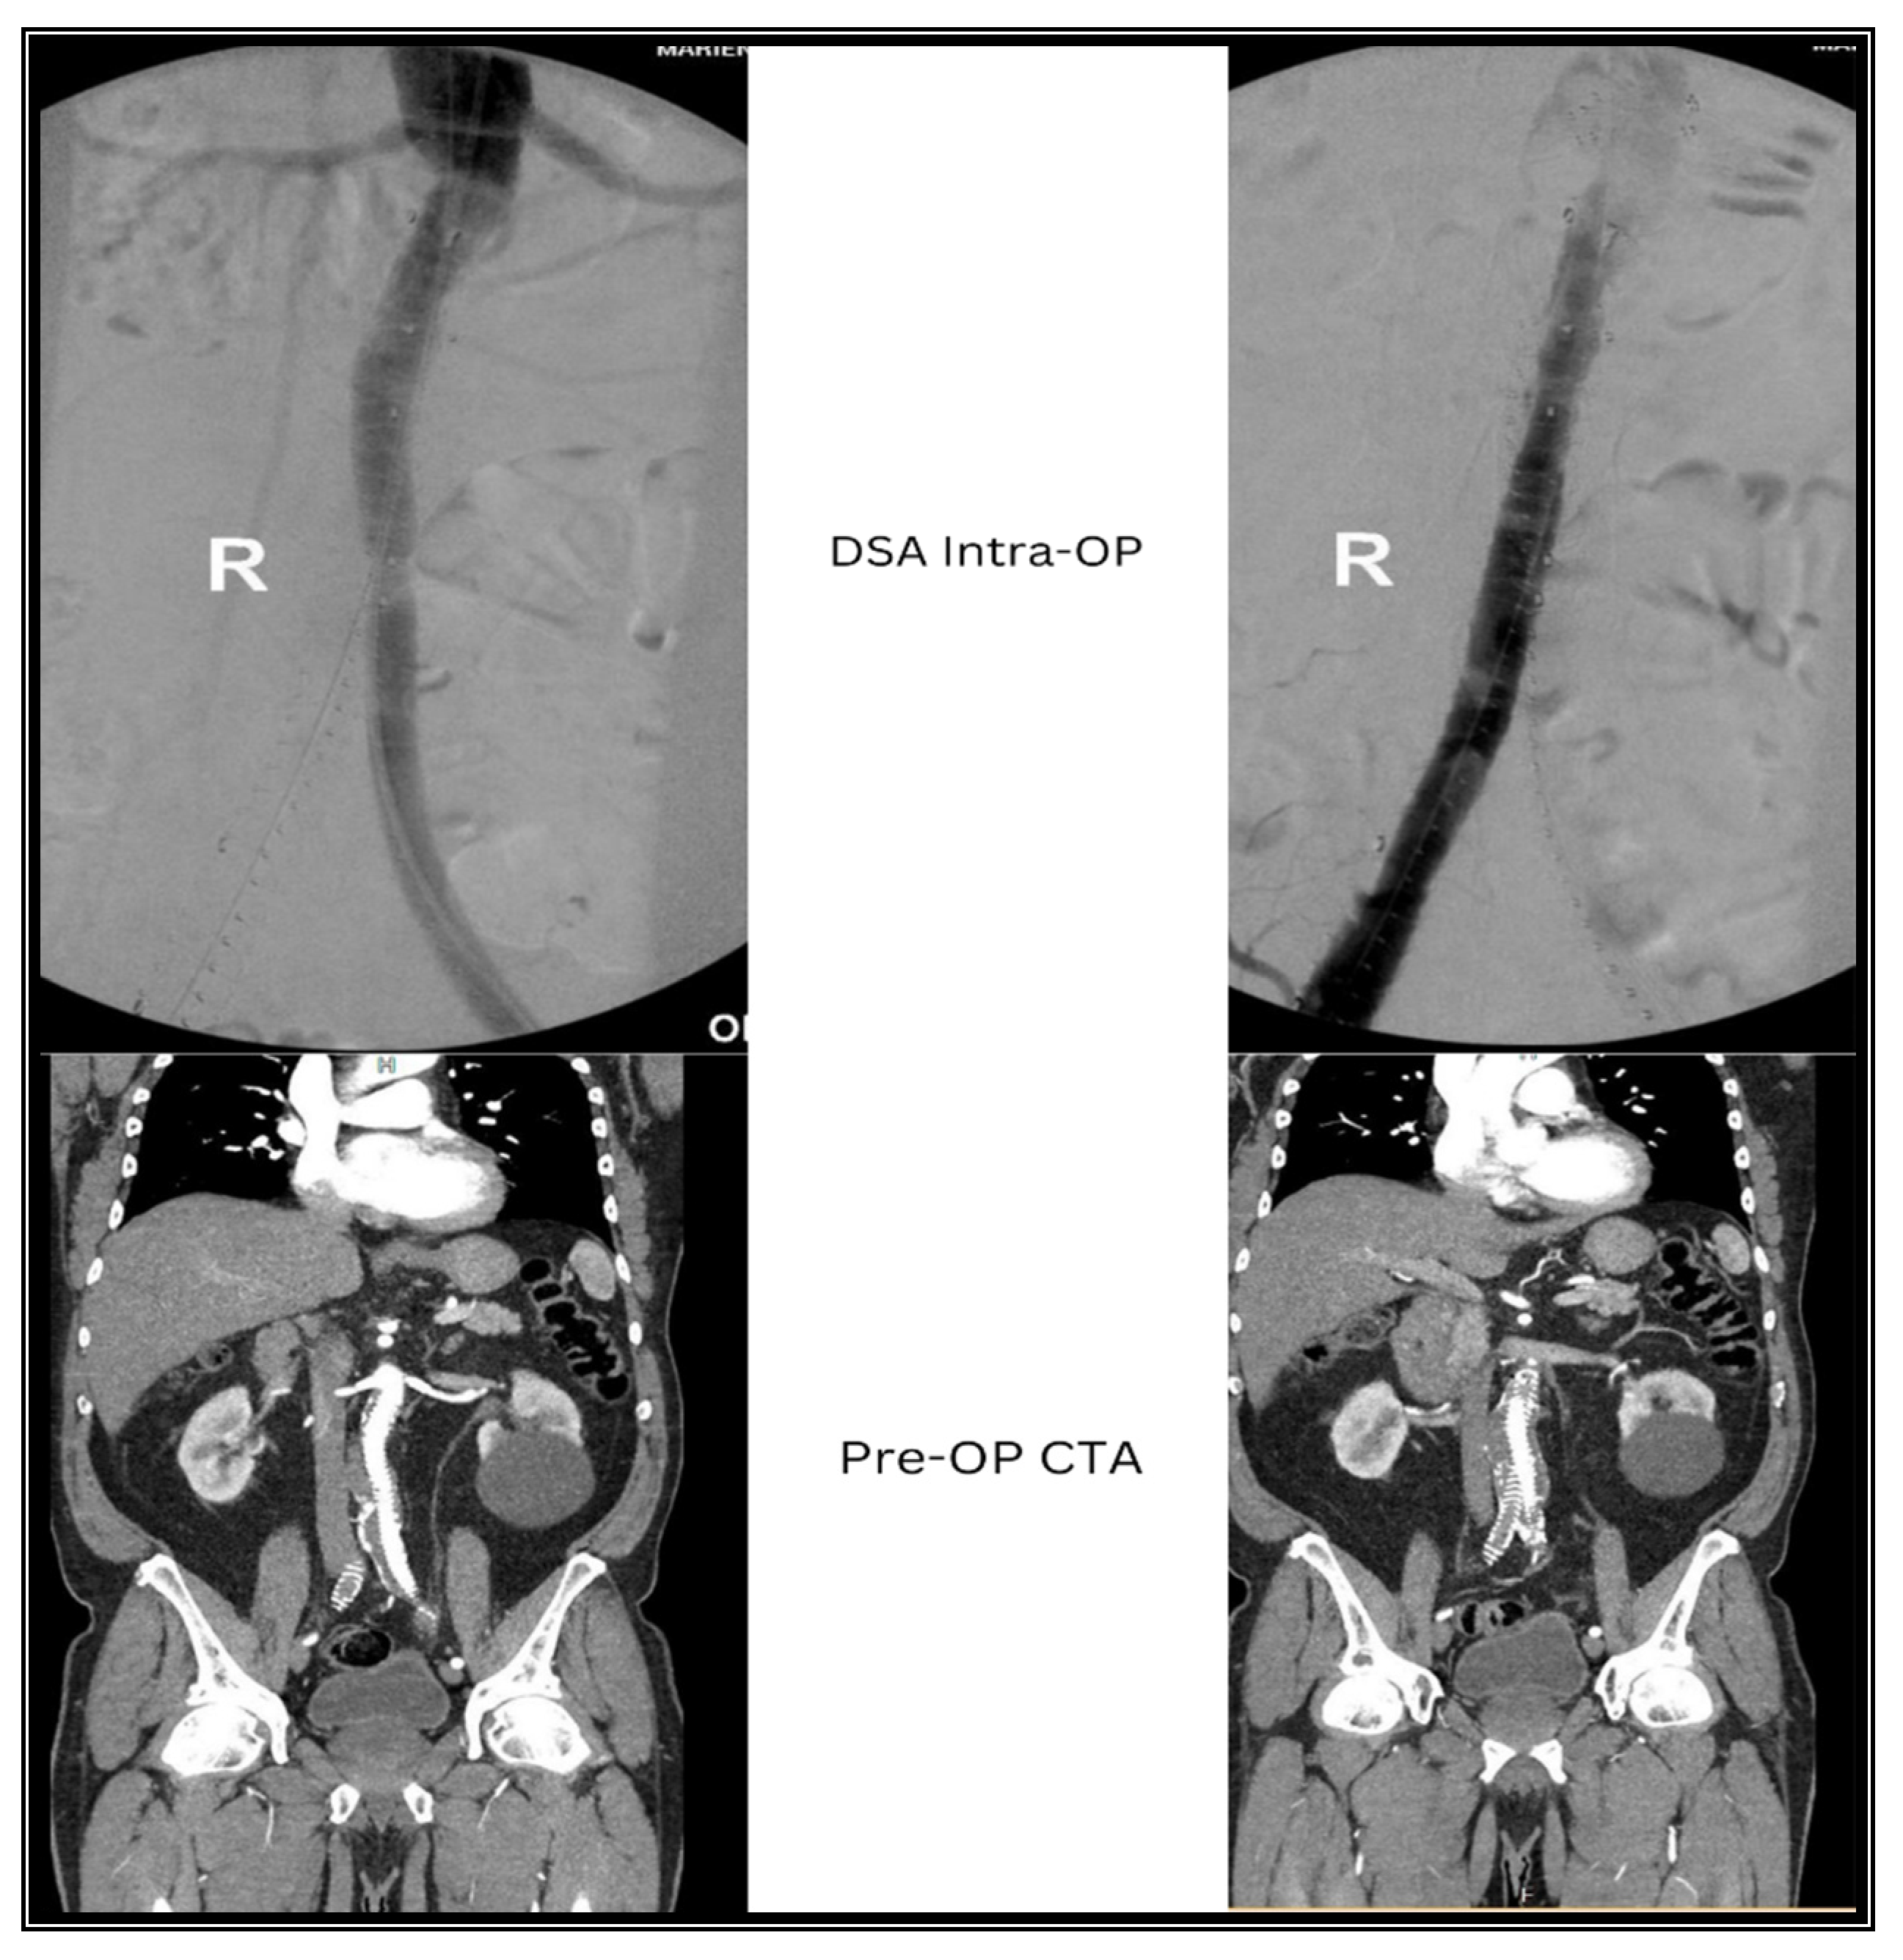

3.2. Case II